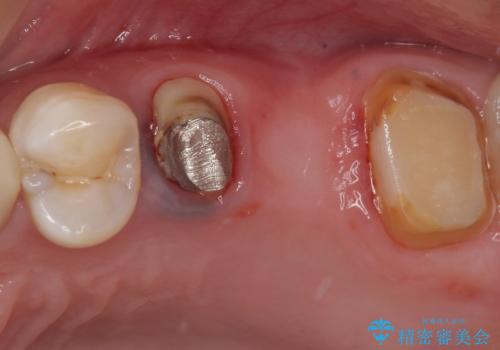

その後、奥歯は痛みのある部分から少しずつ、根管治療やインプラント治療などを行うこととしました。

インプラントが必要となった奥歯は、インプラントが埋入できないほど隣の歯の根尖病変が非常に大きかったため、根管治療を行ったうえで半年ほど待ち、骨が再生したことを確認してからインプラントを埋入しました。期間は長くかかりましたが、大変良い仕上がりとなりました。